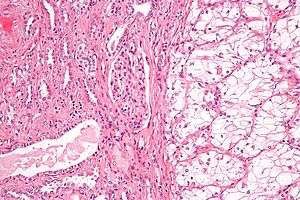

| Micrograph of the most common type of renal cell carcinoma (clear cell)—on right of the image; non-tumour kidney is on the left of the image. Nephrectomy specimen. H&E stain | |

Histopathology

The gross and microscopic appearance of renal cell carcinomas is highly variable. The renal cell carcinoma may present reddened areas where blood vessels have bled, and cysts containing watery fluids.[54] The body of the tumour shows large blood vessels that have walls composed of cancerous cells. Gross examination often shows a yellowish, multilobulated tumor in the renal cortex, which frequently contains zones of necrosis, haemorrhage and scarring. In a microscopic context, there are four major histologic subtypes of renal cell cancer: clear cell (conventional RCC, 75%), papillary (15%), chromophobic (5%), and collecting duct (2%). Sarcomatoid changes (morphology and patterns of IHC that mimic sarcoma, spindle cells) can be observed within any RCC subtype and are associated with more aggressive clinical course and worse prognosis. Under light microscopy, these tumour cells can exhibit papillae, tubules or nests, and are quite large, atypical, and polygonal.

Recent studies have brought attention to the close association of the type of cancerous cells to the aggressiveness of the condition. Some studies suggest that these cancerous cells accumulate glycogen and lipids, their cytoplasm appear "clear", the nuclei remain in the middle of the cells, and the cellular membrane is evident.[55] Some cells may be smaller, with eosinophilic cytoplasm, resembling normal tubular cells. The stroma is reduced, but well vascularised. The tumour compresses the surrounding parenchyma, producing a pseudocapsule.[56]

The most common cell type exhibited by renal cell carcinoma is the clear cell, which is named by the dissolving of the cells' high lipid content in the cytoplasm. The clear cells are thought to be the least likely to spread and usually respond more favourably to treatment. However, most of the tumours contain a mixture of cells. The most aggressive stage of renal cancer is believed to be the one in which the tumour is mixed, containing both clear and granular cells.[57]

The recommended histologic grading schema for RCC is the Fuhrman system (1982), which is an assessment based on the microscopic morphology of a neoplasm with haematoxylin and eosin (H&E staining). This system categorises renal cell carcinoma with grades 1, 2, 3, 4 based on nuclear characteristics. The details of the Fuhrman grading system for RCC are shown below:[58]